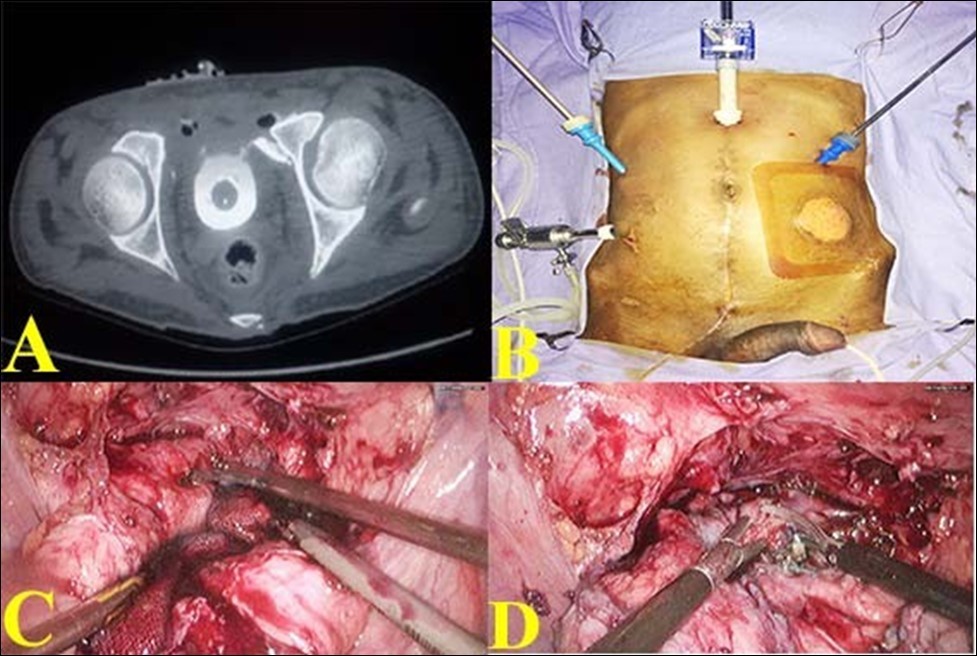

(Figure 2 (G). SPC was reinserted. Bladder was again distended with dilute methylene blue solution to make sure that the closure was watertight. A tube drain was placed. Postoperatively patient made an uneventful recovery. Tube drain was removed on 7thpostoperative day when the drainage was less than 10ml. SPC was removed on the 10thpostoperative day. CT cystogram was done on 21st day which showed no extravasation Figure 2 (H). Patient voided freely on removal of urethral catheter on 21st day.

Figure 2.E. Bladder rent closing with barbed suture ; F. Suturing completed; G. Omental reinforcement over the suture line; H. Post operative CT showing healed bladder.

E. Bladder rent closing with barbed suture ; F. Suturing completed; G. Omental reinforcement over the suture line; H. Post operative CT showing healed bladder.